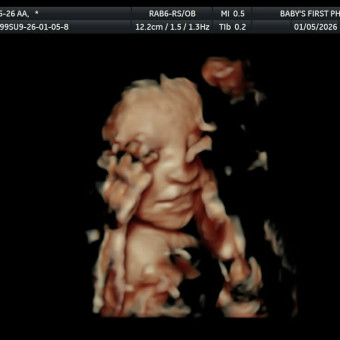

Hello welcome to our baby registry please feel free to contact me with any questions or suggestions thank you for being here and helping us welcome our baby to the world fully and properly prepared 💖😊 Don't forget it's a girl!